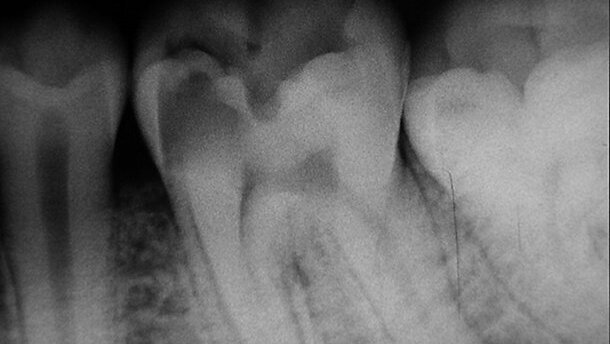

La détermination visuelle de racines supplémentaires nécessite plusieurs radiographies. La prise de premiers clichés sous un angle décalé est indispensable pendant le traitement d’une PMM (Fig. 1a).19,20 Une lime initialement positionnée dans la racine surnuméraire peut donner l’impression d’une perforation.21 Si les résultats radiographiques ne sont pas déterminants, l’utilisation de localisateurs de foramen apical électroniques fournit des informations permettant des lectures assez fiables, pour établir un diagnostic différentiel et confirmer la présence du canal surnuméraire. Selon Walker et Quackenbush, une simple analyse au moyen de radiographies rétrocoronaires interproximales, permet la détection de racines disto-linguales (DL) dans 90 % des cas.18

En 1990, Carlsen et Alexander ont mené une étude où ils ont dénombré 398 molaires mandibulaires définitives pourvues d’une racine surnuméraire en position linguale.22 Cette macrostructure, appelée racine entomolaire ou radix entomolaris, varie considérablement en forme et en courbure. Lorsque cette troisième racine se situe du côté vestibulaire, elle porte le nom de racine paramolaire ou radix paramolaris. Sa forme et sa courbure sont également très fluctuantes (Fig. 1b).23–25 En général, l’axe de la racine est orienté vers la face vestibulaire de la molaire. Il pourrait donc être plus simple de choisir comme point de référence la cuspide disto-vestibulaire plutôt que disto-linguale, ainsi qu’on le fait habituellement. La combinaison de la pente présente au niveau de l’entrée canalaire et de la courbure vestibulaire à hauteur du tiers apical, donne lieu à un canal dont l’instrumentation et l’irrigation sont très délicates. Si l’on veut prévenir des accidents, il est conseillé de choisir un instrument très flexible et de petit diamètre, lors du traitement de la partie apicale.